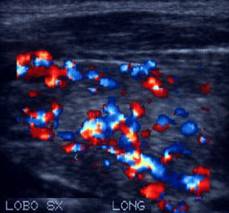

Femeie

de 23 ani. Chist mare (25x29x43mm, 16 cc) in lobul stang, marcant hipoecogen,

cu septe in interi si intarire posteriore.

Examen citologic: pseudochist coloid.

Aceeasi pacienta. Vascularizatie numai in periferie.